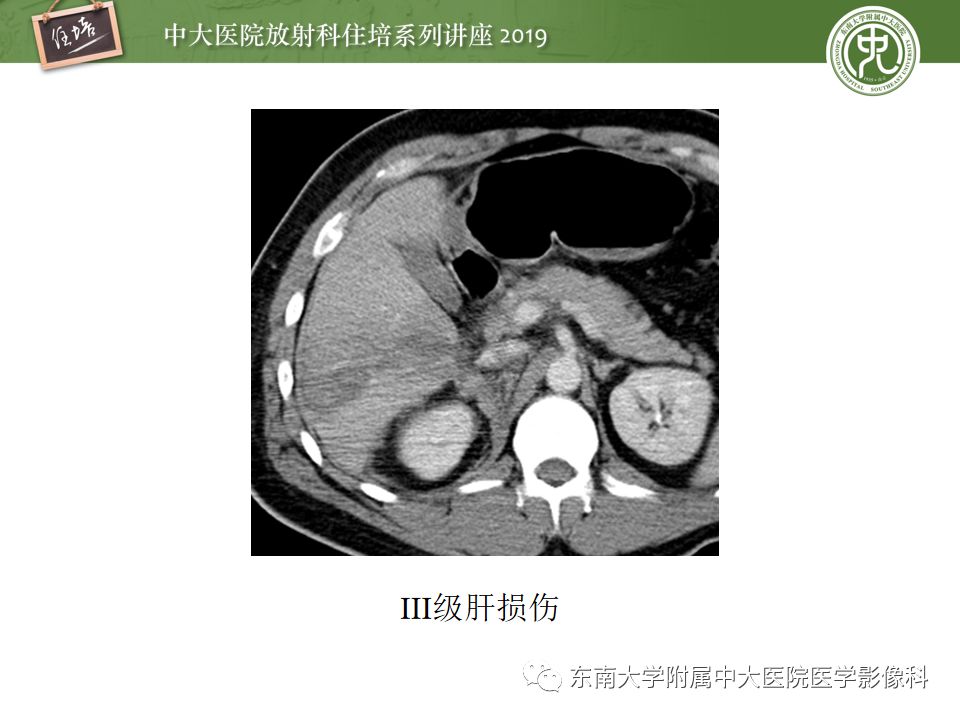

腹腔实性脏器钝性外伤影像诊断